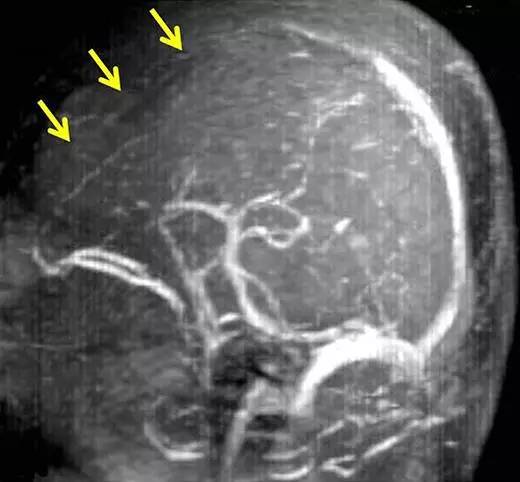

1年后,患者突然出现右侧肢体无力、言语障碍和感觉缺失。此时的MRI和MRA未见明显责任病灶,脑电图同样没有显示癫痫的证据。患者被怀疑脑缺血并接受了抗血小板治疗。本次入院后,患者未再发生震颤,但在入院后第5天,患者右侧肢体无力出现恶化。此时复查MRI,显示从额叶和顶叶的深部髓质静脉到浅表髓质静脉可见多发扩张(图2),此外还可看到围绕这些扩张静脉的脑白质变化。相比之下,双侧基底节、丘脑、脑干和小脑未见显著异常。MR静脉造影证实为上矢状窦前部闭塞(图3)。

图3 住院期间症状恶化时进行的MR静脉造影,显示上矢状窦闭塞(黄色箭头)